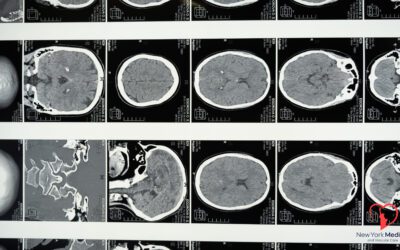

Advancements in Stroke Prevention and Treatment: A Comprehensive Guide At New York Medical Vascular Care, we are at the forefront of incorporating...